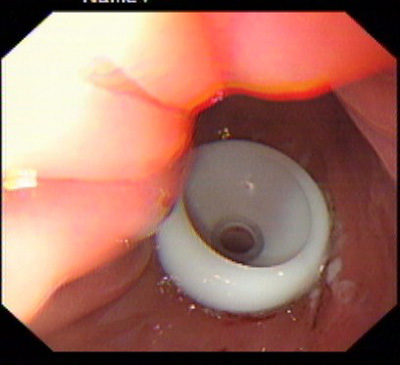

在消化科董蕾主任关心和指导下,消化科王进海教授,张利医师成功地给一位脑出血后吞咽困难的患者实施了经皮内镜下胃造瘘术。

该患者系男性,76岁,脑出血后留有吞咽困难后遗症,不能自主进食,需长期留置胃管供给营养,严重的影响了病人的生活质量和原发病的恢复。经皮内镜下胃造瘘术(Percutaneous endoscpic gastrostomy,PEG)是一种无需常规外科手术和全身麻醉的造瘘技术,可以在胃镜室或病房局麻下进行,因此是一种操作简便、创伤小、安全可靠的方法。该例患者在胃镜室局麻下进行手术,手术过程约10分钟,术后病人无明显不适,3天后即可从造瘘管给食物并出院。

该手术的成功填补了院内空白,丰富了内镜下治疗的内容。对于各种原因造成的长期或较长期不能(一月以上)经口进食者,可通过造瘘管供给病人足够的营养物质,效果优于传统的鼻胃管饲营养,费用又明显低于静脉内营养,是一项值得推广的内镜下较为安全的治疗技术。经皮内镜下胃造瘘术适应证包括:①中枢神经系统或全身性疾病导致的吞咽困难或不能吞咽。如:脑干炎症、变性,脑血管意外,脑肿瘤, 脑外伤;急性呼吸衰竭;系统性硬化症、重症肌无力;完全不能进食的神经性厌食或神经性呕吐导致严重的营养不良,而不能耐受手术造瘘者;②口、咽、喉手术前后及头颈部肿瘤放疗期间,需较长时间营养支持者。③食管广泛瘢痕者;④严重的胆外瘘需将胆汁引回胃肠道者;⑤各种原因所致呼吸功能障碍须气管切开,同时需PEG者;⑥胃肠减压(一月以上的鼻胃管留置者)的目的。